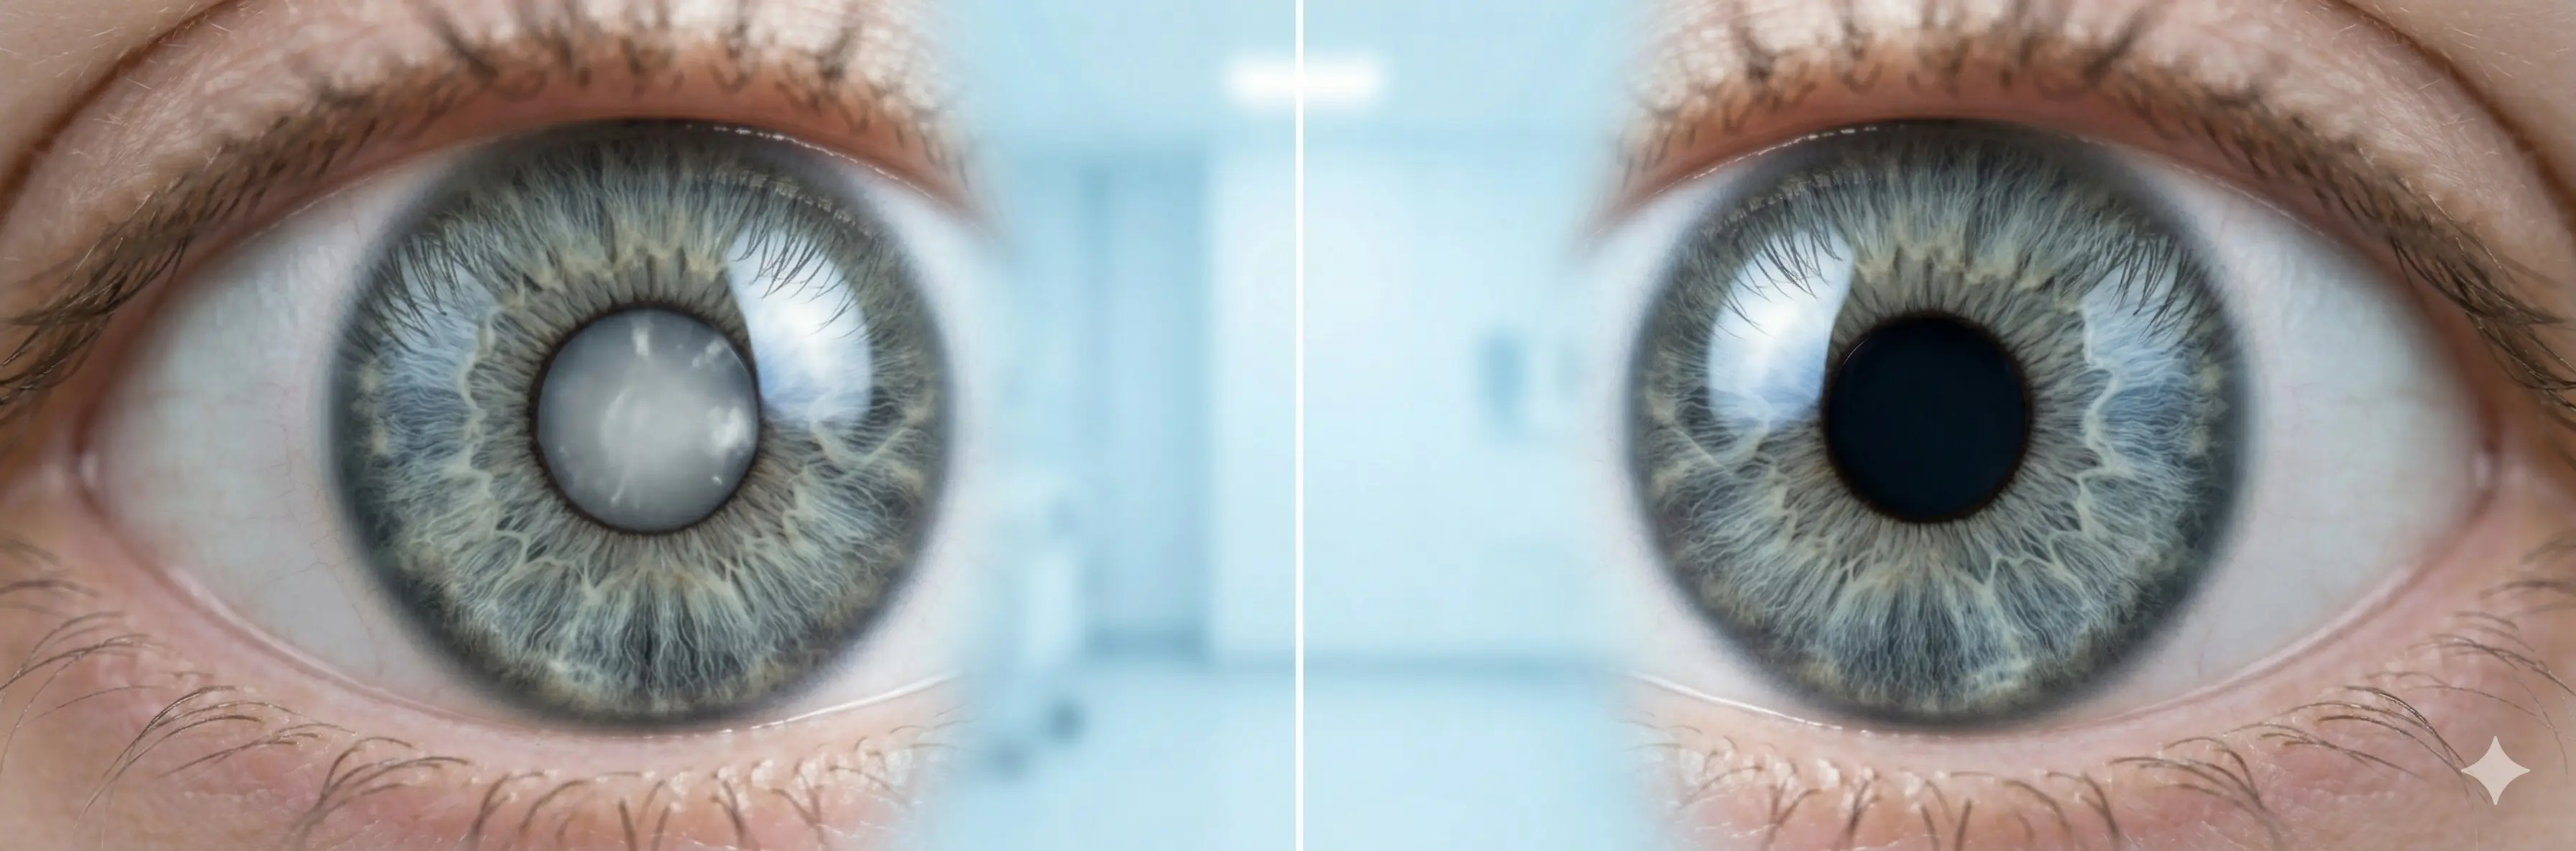

Your doctor scheduled the surgery. But what if you didn't need it? Learn the prevention mechanism most eye doctors never discuss.